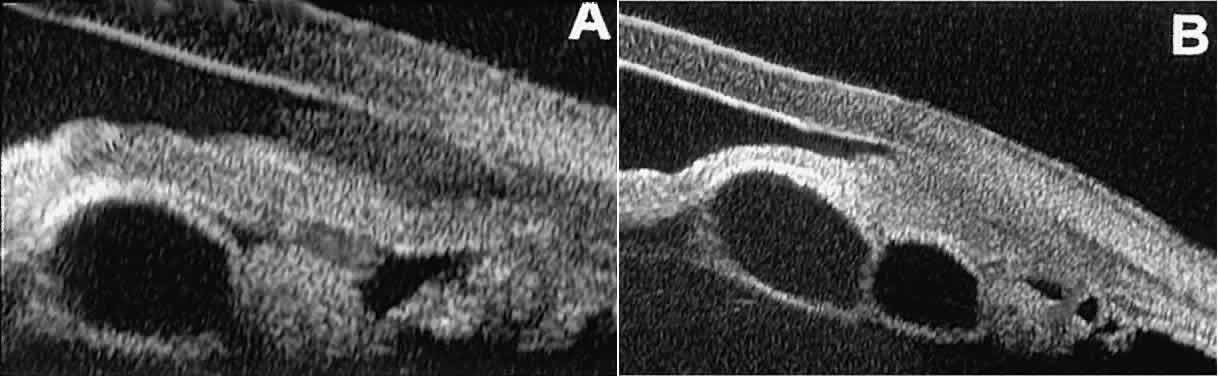

Cystic lesions of the iris and ciliary body can be of four types: primary neuroepithelial cysts, stratified squamous epithelial cysts, neuroepithelial cysts associated with solid tumors, and intratumoral cavities.15 Primary neuroepithelial cysts (see Fig. 22) are very distinct on UBM imaging. These lesions consist of a central sonolucent cavity surrounded by a thin wall of highly reflective neuroepithelial cells. They arise from the posterior surface of the iris (see Fig. 22A), in the iridociliary sulcus (see Fig. 22B and C), or from the inner aspect of the ciliary body (see Fig. 22D). They are often multifocal (see Fig. 22C and D) and bilateral.15 The largest lesions of this type typically occur in or near the horizontal meridians.

Stratified squamous epithelial cysts (Fig. 23) are almost exclusively unilateral and unifocal,15 have substantially thicker walls than do primary neuroepithelial cysts, and usually contain prominent intracavitary particles (desquamated epithelial cells). Almost all such cysts involve the peripheral iris and angle region. Such cysts are usually secondary to prior ocular surgery or laceration in which conjunctival epithelial cells were implanted into the iris stroma.

Fig. 23. UBM features of stratified squamous epithelial cysts of iris. A. Thick-walled implantation cyst of stratified squamous epithelium replacing normal iris. Note intracavitary particles. B. Bilobed stratified squamous epithelial inclusion cyst of iris with prominent intracavitary particles.

Secondary neuroepithelial cysts occur rather frequently in association with solid tumors of the iris or ciliary body.15 On UBM (Fig. 24), such cysts appear quite similar to the primary neuroepithelial cysts described above; however, they are associated with a solid mass arising within the iris or ciliary body.

Fig. 24. UBM appearance of neuroepithelial cysts associated with solid tumors of the iris and ciliary body. A. Single neuroepithelial cyst associated with iris melanoma. B. Multiple neuroepithelial cysts associated with iridociliary melanoma.